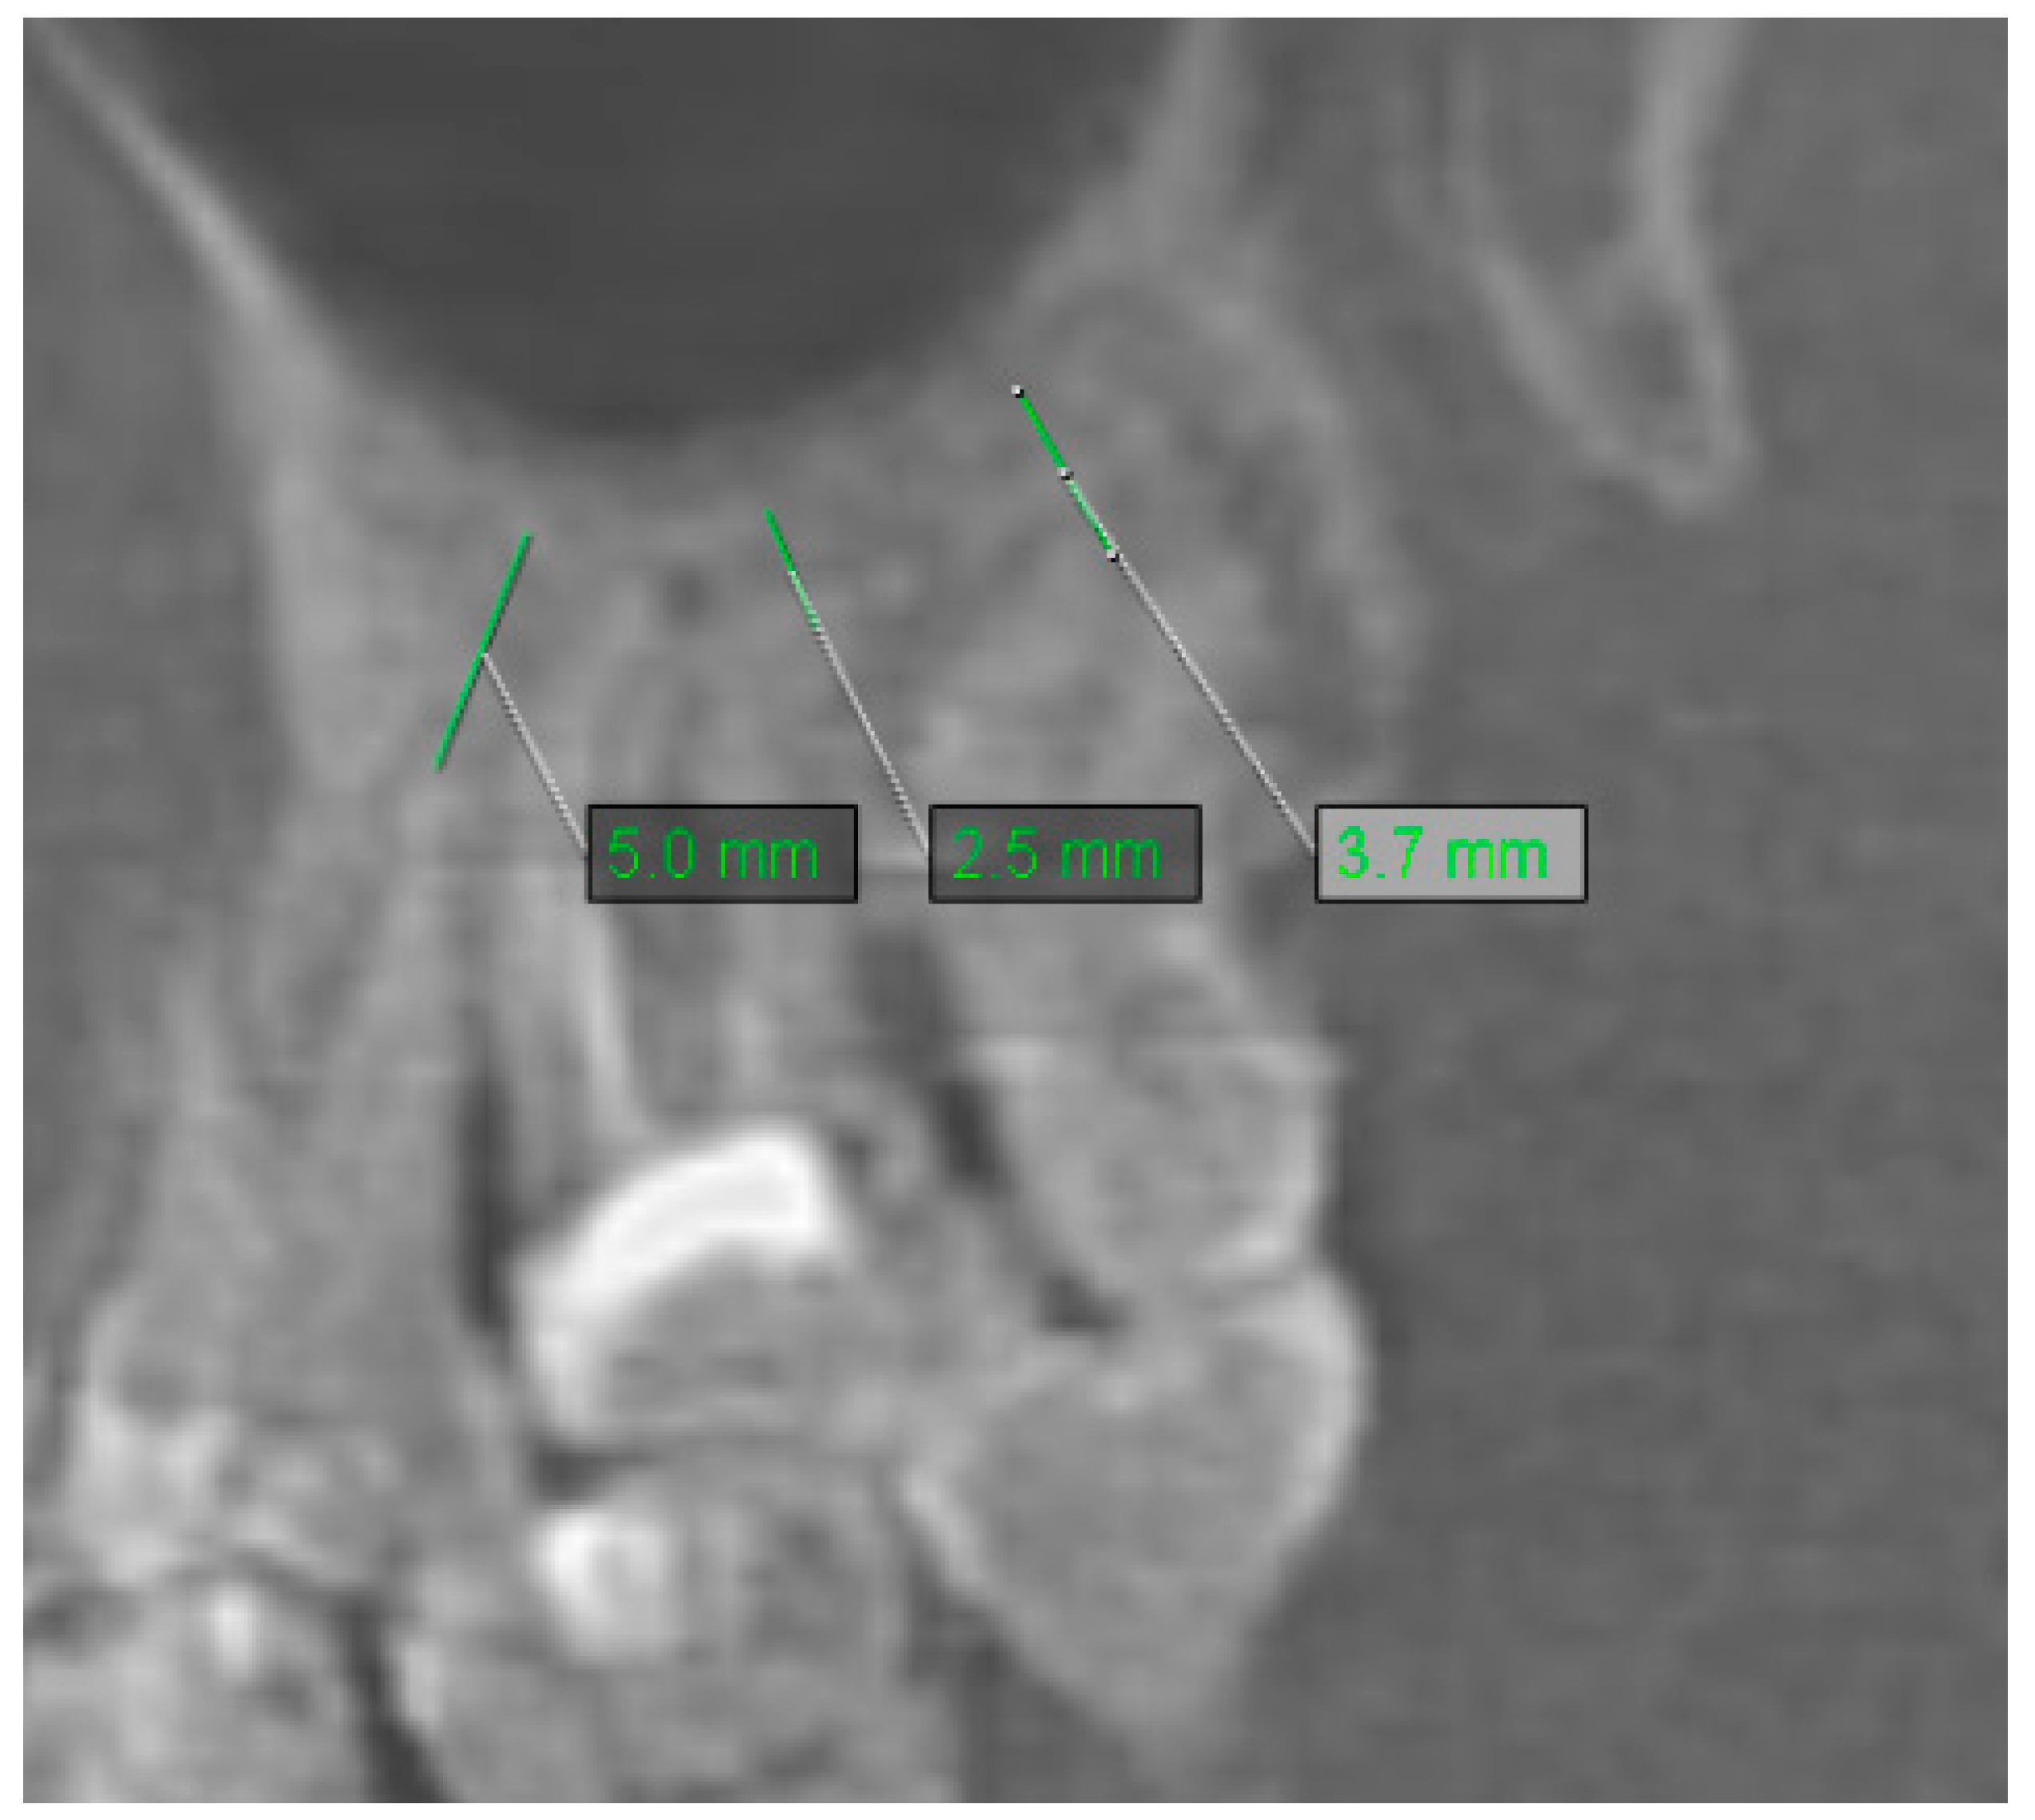

2.2. Assessment of Anatomic Relation between Teeth and Maxillary Sinus

2.3. Assessment of Periodontal Bone Loss

2.4. Assessment of Mucosal Thickening